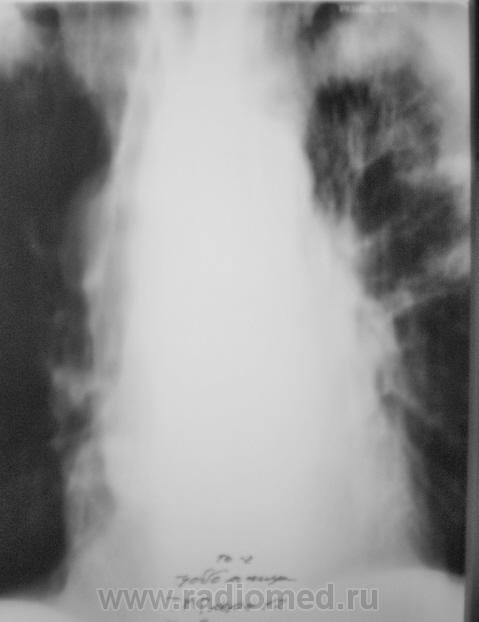

После первой госпитализации в областном спец. ЛПУ, при выписке, в виде контроля динамики, была сделана рентгенограмма в прямой проекции, которая, на мой взгляд, имеет определенный интерес.

В последнее время пациент затежелел и был госпитализирован в областное ЛПУ, где было проведено несколько исследований.

1. Исследовавние.